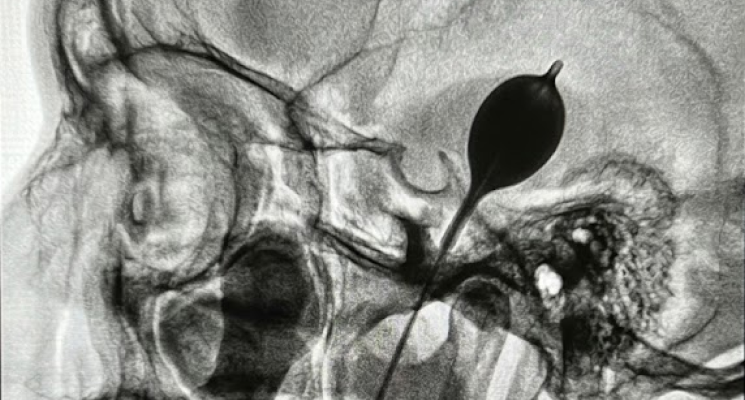

Feito da mesma forma que anterior, só que ao invés de cauterizar por um eletrodo, é passado um cateter com um balão na ponta. Este balão é insuflado do lado do nervo por alguns segundos “esmagando” as fibras que transmitem a dor, e consequentemente desligando a dor.